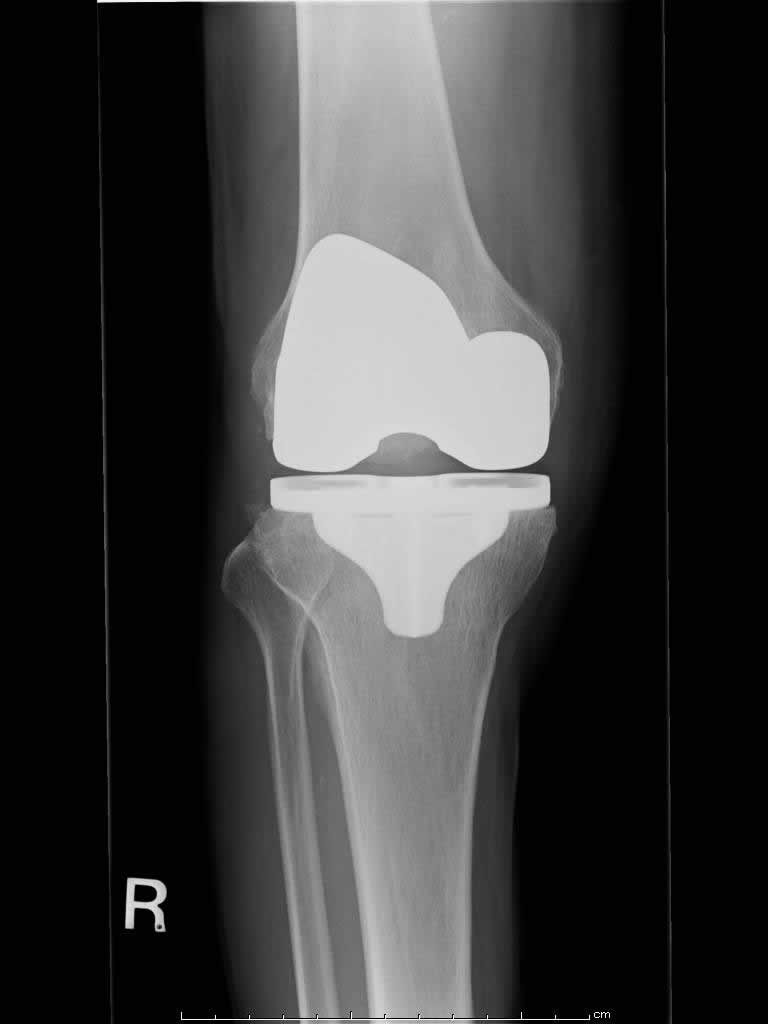

人工膝関節置換術(TKA)(変形性膝関節症)

加齢や怪我などにより、傷んだ軟骨と骨を削って、人工関節に置き換えます。

【術後】